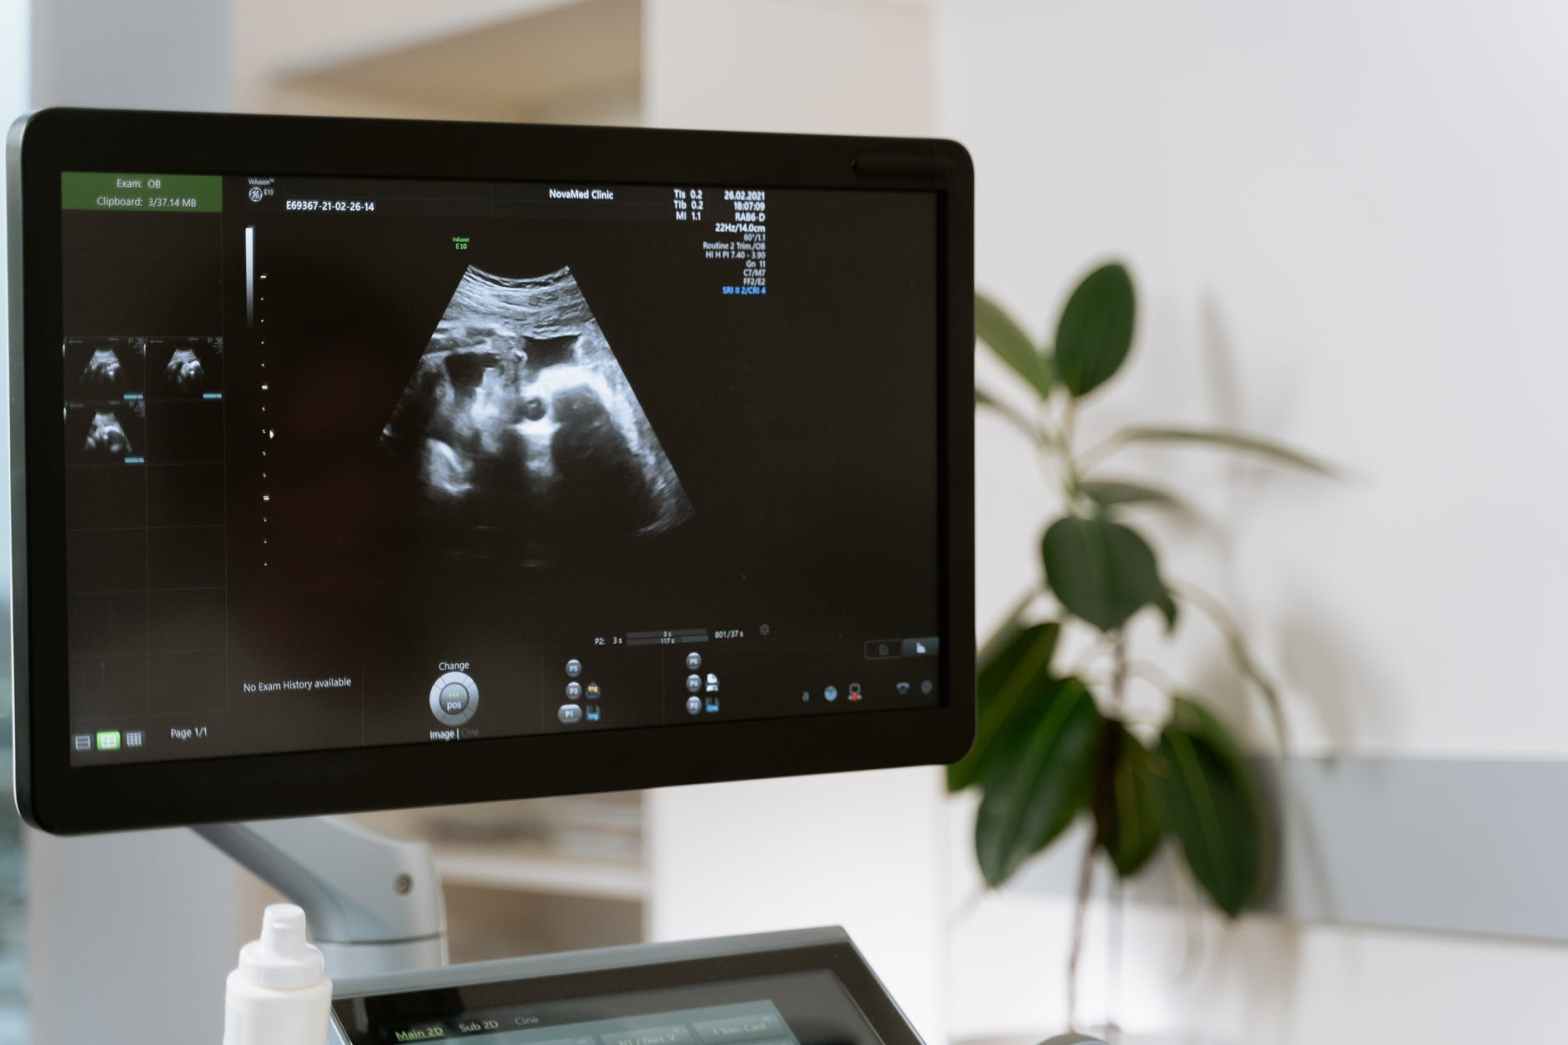

Una prueba de ultrasonido 4D (1) es una forma de reproducir una imagen en movimiento de su bebé dentro de su útero. El ultrasonido 4D usa ondas de sonido para crear esta imagen en movimiento. En una ecografía 3D, puede ver una imagen tridimensional de su bebé. Un ultrasonido 4D lleva esta experiencia al siguiente nivel. Crea un efecto similar a ver un video en vivo. Usando esta tecnología, puedes ver lo que tu bebé está haciendo en ese momento dentro de tu matriz. De hecho, ¡incluso puede ver si su bebé está bostezando o sonriendo en ese momento en particular!

Mientras se realiza la ecografía 4D, su médico la ayudará a ver a su bebé en la pantalla. Esto le permitirá saber qué está haciendo su bebé en ese momento.

La forma de los resultados que obtendrá de su ultrasonido 4D puede variar según su médico y el procedimiento médico. Si bien algunos resultados se dan en forma de una imagen de su bebé, algunos médicos pueden entregarle una película 4D adecuada.